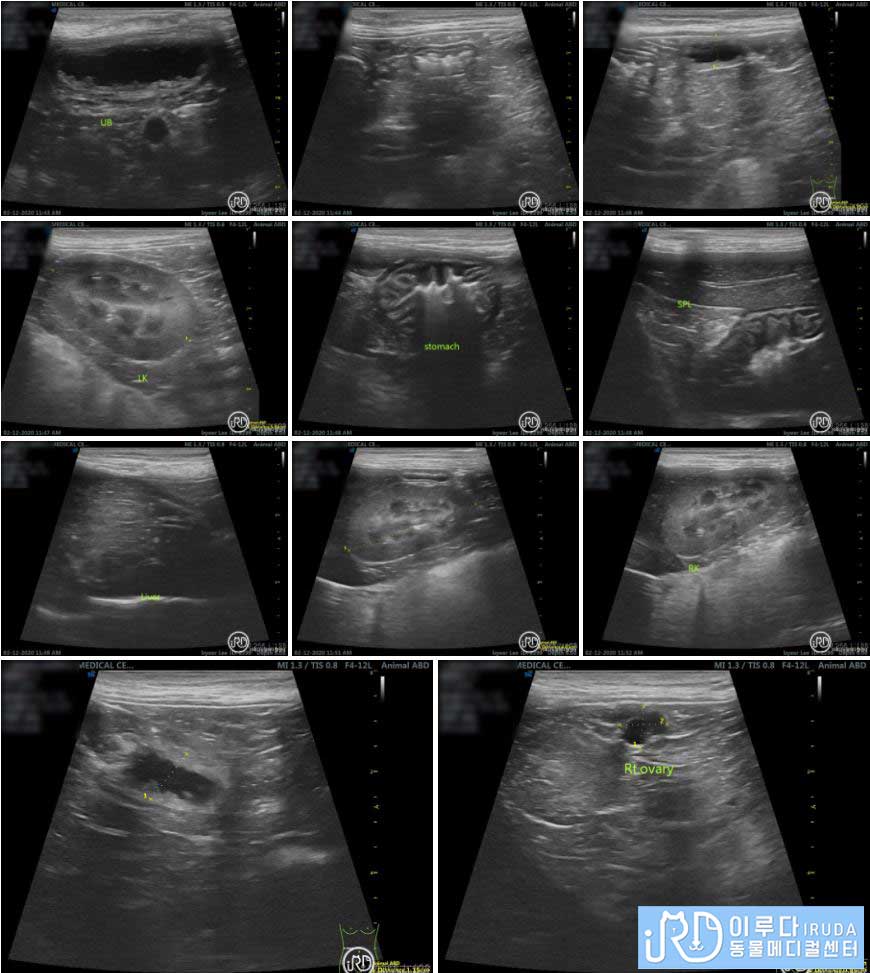

복부 초음파를 통해 살펴본 결과, 장 내에 있는 다수의 가스가 확인되었습니다. 또한 간, 신장, 방광 등의 장기에는 문제가 없었지만 자궁의 크기가 비대하다는 것을 확인할 수 있었습니다. 방사선 검사와 복부 초음파를 통해 확인한 결과, ㅂㅇ는 자궁 수종과 장염으로 진단되었습니다.

복부 초음파 검사